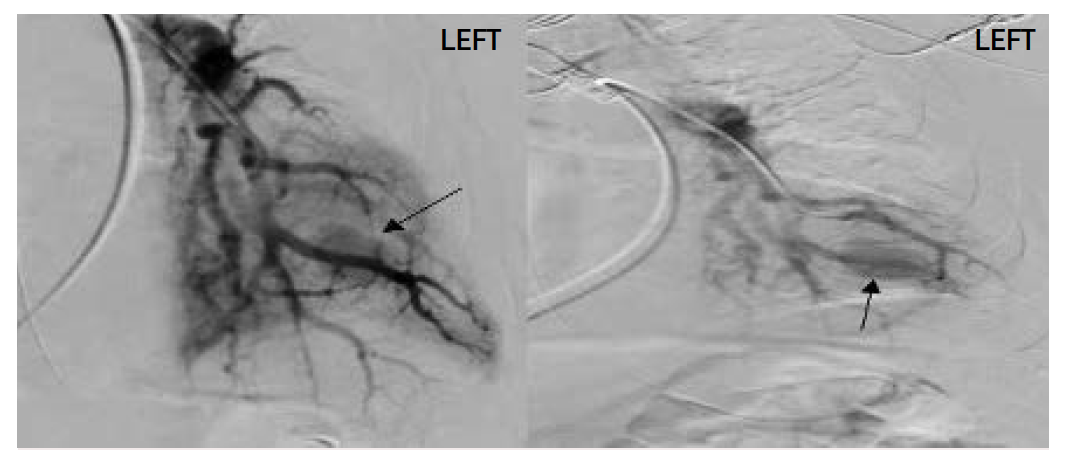

Based on CTA, the interventional radiology (IR) team was consulted, and they performed a pulmonary angiography. A large pseudoaneurysm arising from a left lower lobe segmental pulmonary artery branch was found (Figure 1), and it was successfully embolized (Figure 2).

On postoperative day (POD) 1, the patient was generally improving on minimal ventilatory settings, hemodynamically stable, and the anemia was improving. Respiratory cultures taken earlier via bronchoscopy were all negative. On POD 2, the patient was successfully extubated, the anemia improved to better than baseline, and the patient was transferred from the ICU to the hospital medicine service. On POD 3, a CT chest scan with and without contrast showed mild interval improvement in the left lower lobe consolidation without active contrast extravasation or pooling of contrast on arterial or delayed imaging. This supported the absence of residual pseudoaneurysm, and the patient was discharged on POD 5.

Two months earlier, the patient developed methicillin-sensitive Staphylococcus aureus (MSSA) sepsis, with subsequent septic pulmonary and vertebral emboli. The source of sepsis was an infected permanent pacemaker implant, which was being used for management of the patient’s sick sinus syndrome. There were many septic pulmonary emboli scattered in the lungs, one of which was in the left lower lobe and was associated with abscess. The site of this one matches exactly the site of the pseudoaneurysm discovered at the current presentation, supporting the mycotic nature of this pseudoaneurysm. Furthermore, there is no explanation of congenital disease, trauma, or vasculitis that can support another diagnosis with a more logical explanation than mycotic aneurysm. The pseudoaneurysm remained asymptomatic until hematogenous seeding with K. pneumoniae urosepsis induced it to rupture 2 months later.